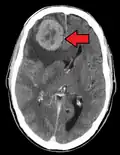

CT image of multiple liver metastases -

CT image of a lung metastasis -

Metastatic cancer in the lungs -

Metastases from the lungs to the brain -

Metastases from the lungs to the pancreas